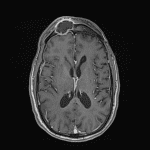

- Overlying thin peripherally-enhancing subgaleal collection along the superior margin of the frontal lesion with associated restricted diffusion and T2 signal hyperintensity and enhancement in the right frontal scalp

- Mass effect on the subjacent right frontal lobe with associated dural thickening and enhancement

Expansile lesion in the right frontal sinus with peripheral enhancement and central restricted diffusion measuring 3.5 x 2 x 2.5 cm. This appearance is concerning for a mucopyocele (infected mucocele). Associated mass effect on the subjacent right frontal lobe with associated dural thickening and enhancement but no discrete extraaxial collection or evidence of cerebritis.

Overlying thin subgaleal abscess (along the superior margin of the collection) and cellulitis.